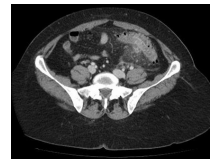

Homem 66 anos, dor em abdome inferior e febre. Leuco – 17.100. Analisando a TC de abdome abaixo, podemos

identificar